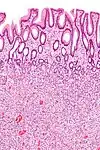

| Hyperplastic polyp of the stomach | Stomach | Elongated, tortuous, and cystic foveolae separated by edematous and inflamed stroma.[4] | ![]() |

Gastric hyperplastic polyposis | |